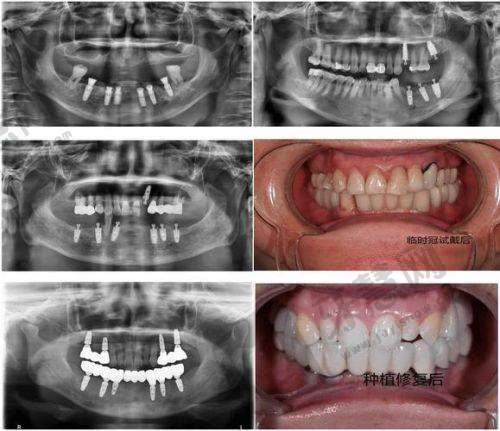

上榜理由:作为延边地区仅此的三等甲医院口腔科,该科室拥有吉林省起初进的口腔诊疗设备,包括德国西诺德数字化CBCT和丹麦3shape口腔扫描仪,能实现0.1mm精度的种植方案设计。科室主事金医生从事口腔临床工作30余年,擅长上颌窦提升、骨增量等复杂种植手术,年均完成种植病例超800例。

技术优势:特殊引进"数字化导板精细种植技术",通过术前3D重建口腔模型,术中全程导板引导,将种植误差控制在0.5mm以内,手术时间比传统方式缩短40%,术后肿痛发生率低于5%。对于牙槽骨条件差的患者,可开展同期骨移植手术,避免二次创伤。

收费价目:-韩国登腾种植体:8000元/颗-瑞士ITI种植体:12000元/颗-全口种植修复:8-15万元-3D数字化种植导板:1500元/例